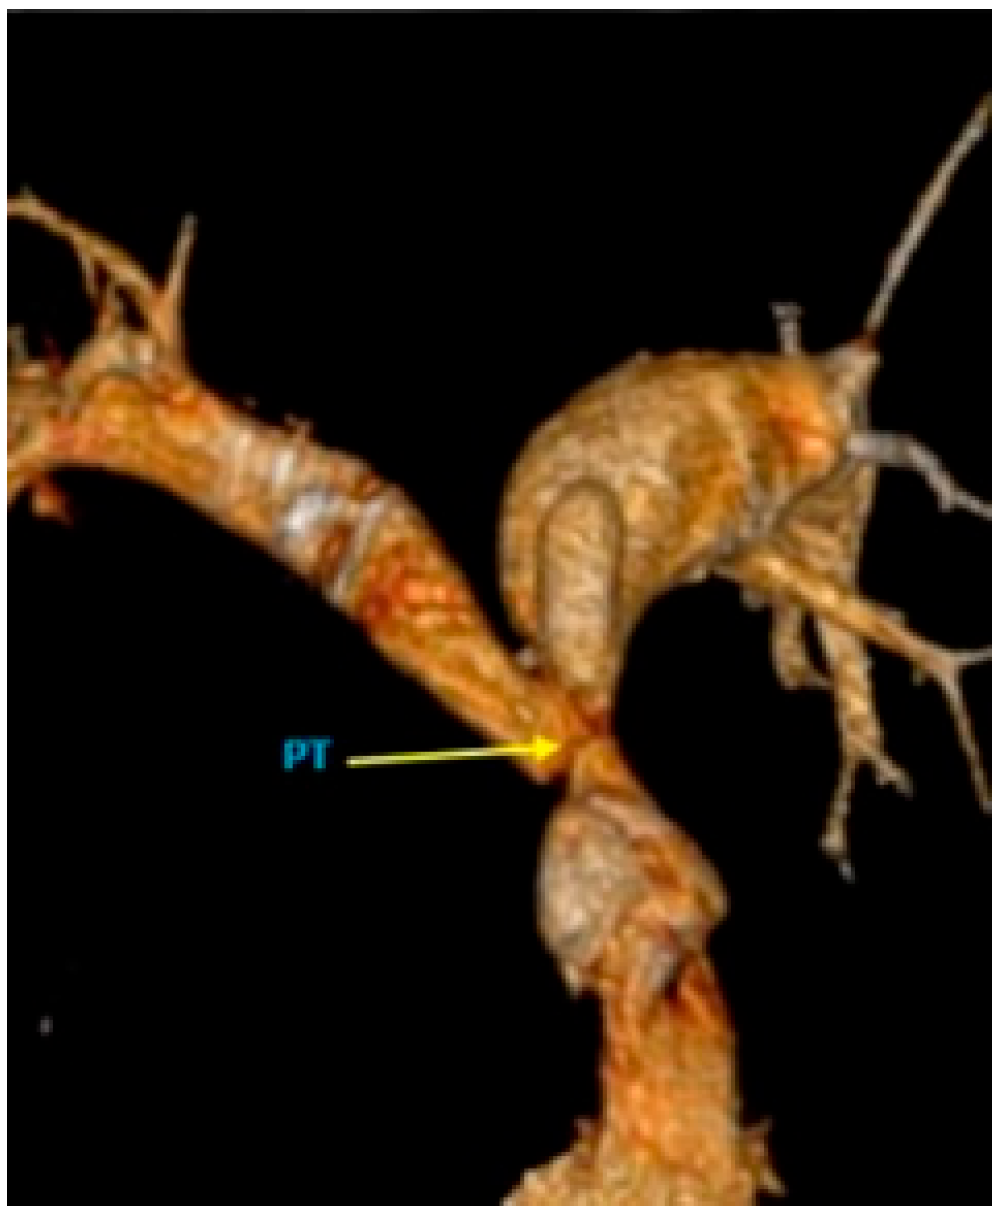

The Case of a 44-Year-Old Survivor of Unrepaired Tetralogy of Fallot, Right Aortic Arch and Abdominal Aortopulmonary Collateral Vessels

2. Case Report

2.1. Initial Work Up

2.2. Diagnosis and Management